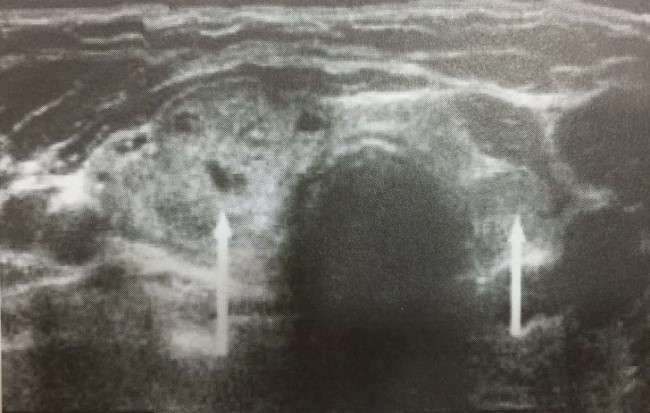

참고) TFT 해석

출처 : doi : 10.31128 / AJGP-10-20-5693